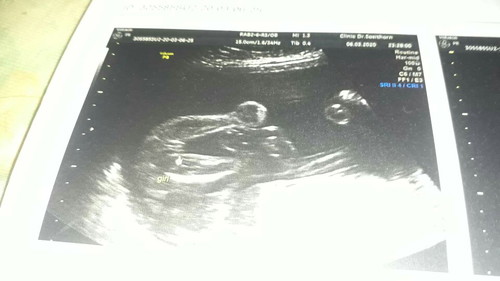

ผู้หญิงค่ะ บ้านนี้ซาวแล้วเป็นกลีบแบบนี้เลยหมอบอก ญ ค่ะ และในรูปล่างลูกศรชี มีเขียนว่า girl ค่ะ

หญิงจ้า แคมชัด ในใบซาวด์ก็ระบุว่าหญิงชัดเจนจ้า

Girl แปลว่า ผู้หญิงค่ะ หมอก็เขียนไว้อยู่นะคะแม่

ผู้หญิงค่า แฮมเบอร์เกอร์ เป็นกลีบมาเลยค่ะแม่

มาเป็นกลีบขนาดนี้ น้องเป็นหญิงแน่นอนจ้าแม่